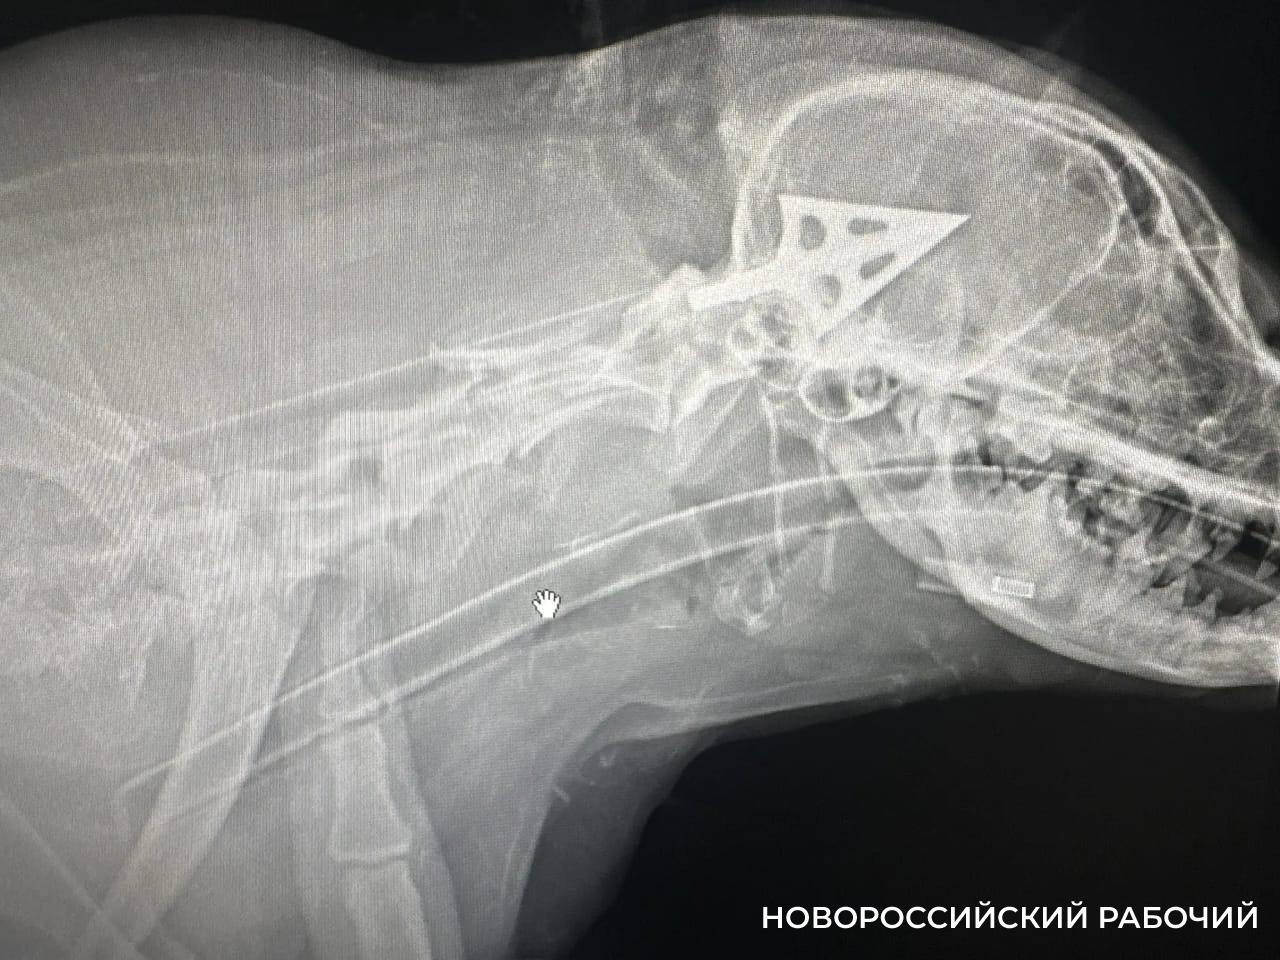

Соседи рассказали нам, что это уже не первый случай, когда в округе находили собак, умерших от ранения стрелами. Стрела — арбалетная, тяжелая. У нашей дворняги, в ветклинике ее назвали Булкой, было три входных отверстия.